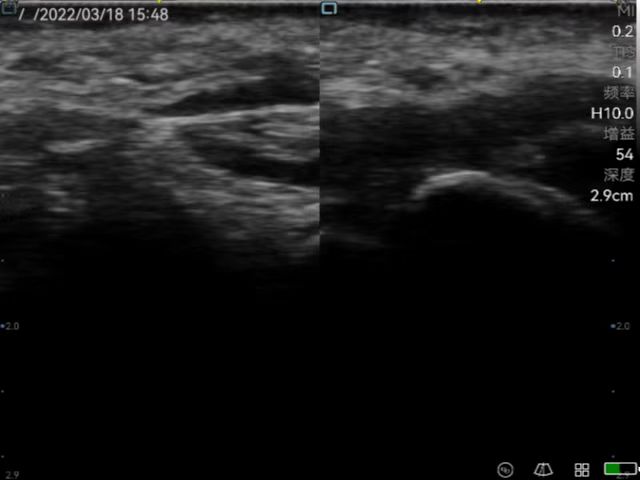

Musculoskeletal ultrasound technology (referred to as musculoskeletal ultrasound) has developed rapidly domestically, and has been continuously promoted and applied in clinical practice. It has become the first choice or gold standard in the diagnosis and treatment of many diseases, such as peripheral nerve diseases, muscle and tendon acute and chronic diseases, early diagnosis and differential diagnosis of rheumatism and rheumatoid diseases. Rehabilitation medicine has developed rapidly in recent years. With the aging of the population, the development of the hierarchical diagnosis and treatment system, and the emergence of precision medicine, medical imaging, especially ultrasound medicine, plays a very important role in rehabilitation medicine. At present, rehabilitation medicine in our country relies on traditional physical examinations, and its blindness, randomness, untargetedness and lack of objective indicators for judging efficacy have attracted more and more attention. Musculoskeletal ultrasound has the advantages of non-invasiveness, convenience and practicality which can be used as the first-choice imaging examination for rehabilitation medicine. Ultrasound positioning and ultrasound-guided puncture injection technology have become the "third eye" of rehabilitation physicians which has an irreplaceable role in manipulative therapy, rehabilitation equipment therapy, injection therapy and sports rehabilitation, etc.

Peri-articular injection to help diagnose and guide injection of anti-inflammatory drugs for frozen shoulder.

Application in joint ultrasound (wrist, shoulder, elbow, hip, knee, ankle, etc.); Therapeutic application of muscle, tendon, myofascial pain syndrome; Application in urinary system rehabilitation; Application of ultrasound-guided botulinum toxin injection therapy; Applications of Neurosonography; Applications of Cardiac Ultrasound; Application of interventional ultrasound (interventional treatment of joint disease, cystic disease); Expanded application of ultrasound in traditional medicine (ultrasound visualization acupotomy technology); Application of pelvic floor ultrasound in rehabilitation of diseases; Application of ultrasound-guided puncture in pain.